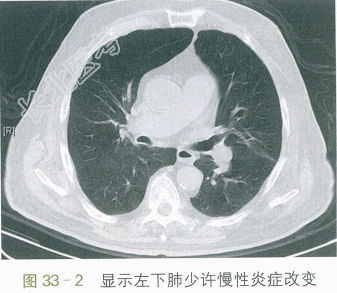

T37.2℃,P110次/min,R25次/min,BP145mmHg/88mmHg,神志清,神萎,呼吸急促,口唇发绀,球结膜水肿,颈软,颈静脉充盈,气管居中,桶状胸,双肺叩诊清音,听诊呼吸音粗,呼气相延长,两肺可及哮鸣音,未及湿啰音。HR110次/min,律齐,可及早搏。双下肢轻度凹陷性水肿。神经系统体征(-)。

胸部平扫CT:肺气肿,两肺少量慢性为主炎症。如图33-1、图33-2所示。